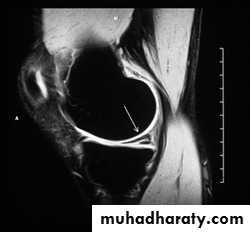

.Meniscal & ligamentous tears in the knee .

.Rotator cuff tears of the shoulder .